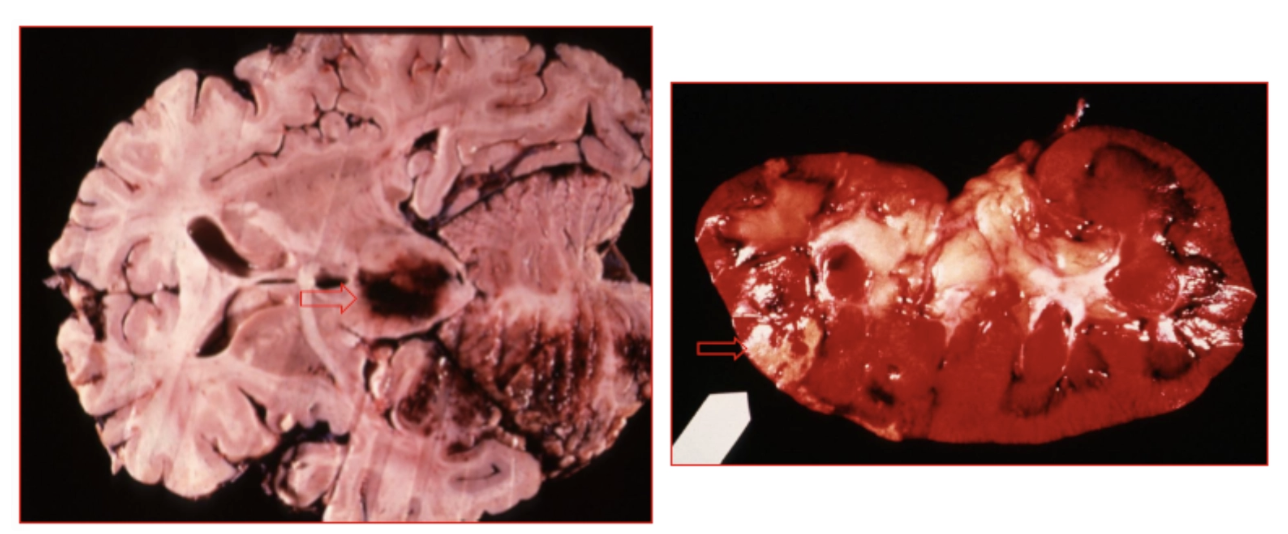

Cardiopatía isquémica crónica